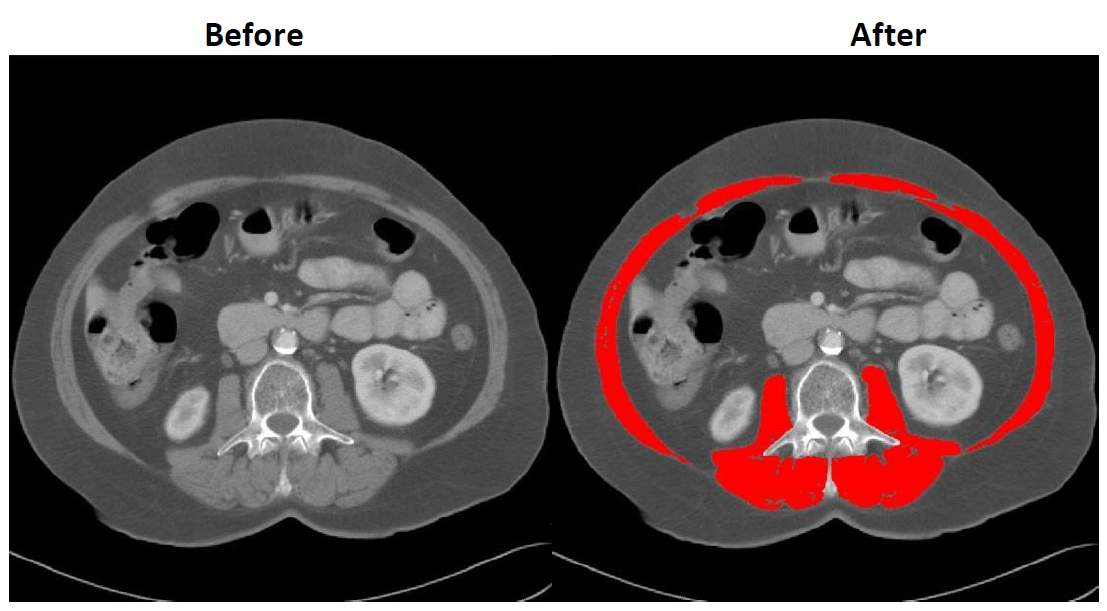

·For skeletal muscle analysis, all muscles at the L3 region will be analyzed (TAG 1- Red, HU Range: -29 to +150)

Be careful not to analyze organs that might be touching the skeletal muscle such as intestines, liver, or kidneys as muscle.